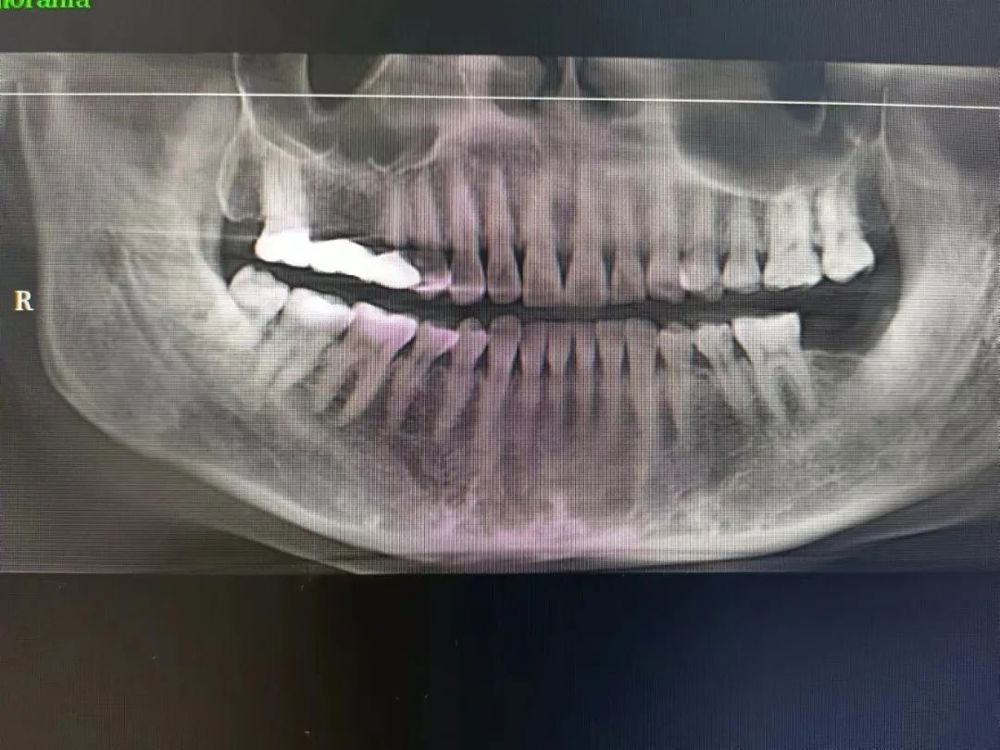

三、種植牙技術

目(mù)前,社會上很多(duō)人被牙齒缺失所(suǒ)困擾,牙齒缺失不但影響人的咀嚼和(hé)語言功能,對於人的(de)麵(miàn)部(bù)美觀也是一種影響,甚至有些人因(yīn)缺失牙齒而(ér)不願意張口說話,種植牙被譽為(wéi)人類“第(dì)三(sān)副牙齒”,因其舒適(shì)、美觀(guān)、功能(néng)好而被缺牙患者追捧。經衛生(shēng)健康委批準,我院於2023年(nián)3月18日正式(shì)開展種植(zhí)牙技術,開(kāi)展當天門診手術7例共計14顆植體,術(shù)後1天回訪患者表示無紅腫、無疼痛症狀(zhuàng),術後(hòu)7天回訪(fǎng)一切良好無異常,術後10天拆線創口愈合良好,自開展口(kǒu)腔種植手術以來,有許多患者紛紛到科裏(lǐ)進行相關谘詢和(hé)檢查,更是不斷有患(huàn)者預約意向種植,我院嚴格按照江(jiāng)西省醫療保障局、江西省衛生健康委員(yuán)會(huì)關於(yú)公布實施口腔種植類醫療服務價格有關事項的通知—贛醫保字《2023》3號文(wén)件執行操作,在手術診療中,嚴(yán)格操作流程,減少感染風險。我院(yuàn)口腔種植技術的成功和發展,不僅完善了傳(chuán)統牙齒修複(fù)技術的不(bú)足,而且在功能與(yǔ)美觀上給了(le)人們嶄新的體驗,我院致力於提供一站式口腔種植診療服務,必將為(wéi)本縣及周邊缺(quē)失牙患者找回美麗、自信的微笑。

案例(lì)一

種植前與種植後

案例二

種植前與種植(zhí)後